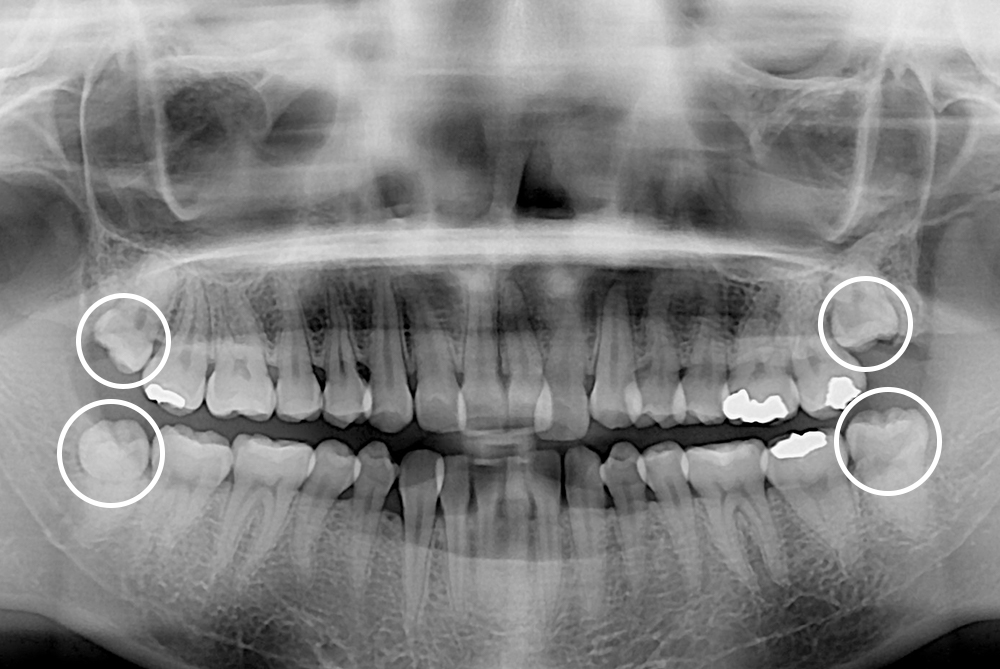

[사랑니] 매복 사랑니 발치

치료후 : 2018-06-25

세종치과는 구강악안면외과학 박사이신 원장님이 발치하는 치과입니다.